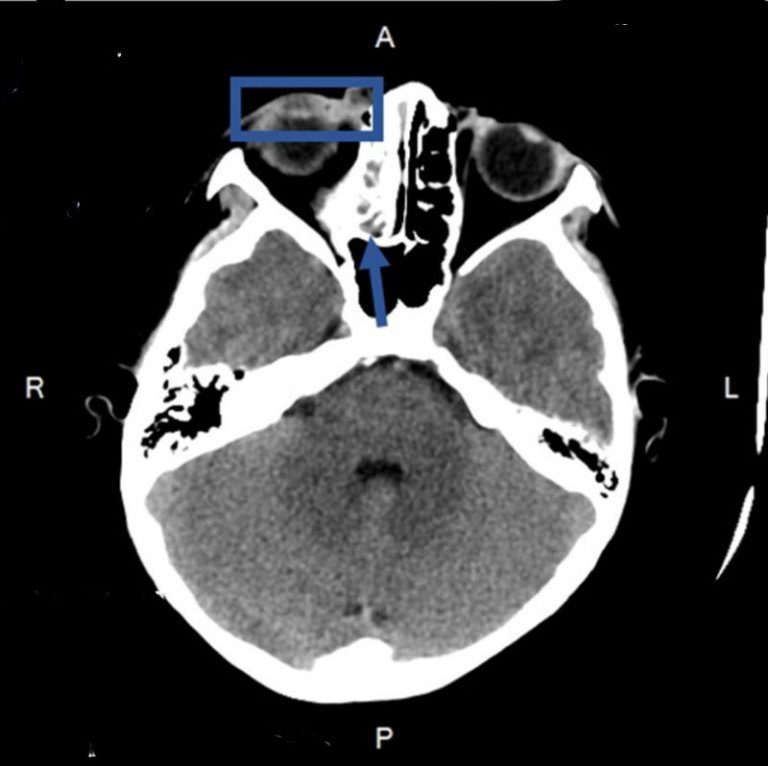

▲CT 影像顯示藍框處為右眼眼瞼發炎腫脹,箭頭處則是右側鼻竇炎。(圖/新竹臺大分院提供)

新竹臺大分院小兒部許瑋芸醫師診察後發現,男童右眼下眼瞼紅腫並壓痛,範圍超過下眼瞼,進一步抽血檢查顯示白血球數值及發炎指數顯著上升,醫療團隊隨即進行電腦斷層檢查並安排住院,經評估與檢查確診為隔膜前(眼眶周圍)蜂窩性組織炎,立即給予男童靜脈抗生素治療,病況逐漸改善,後續改以口服抗生素治療,後順利出院返家休養,並於門診追蹤,目前已完全康復。